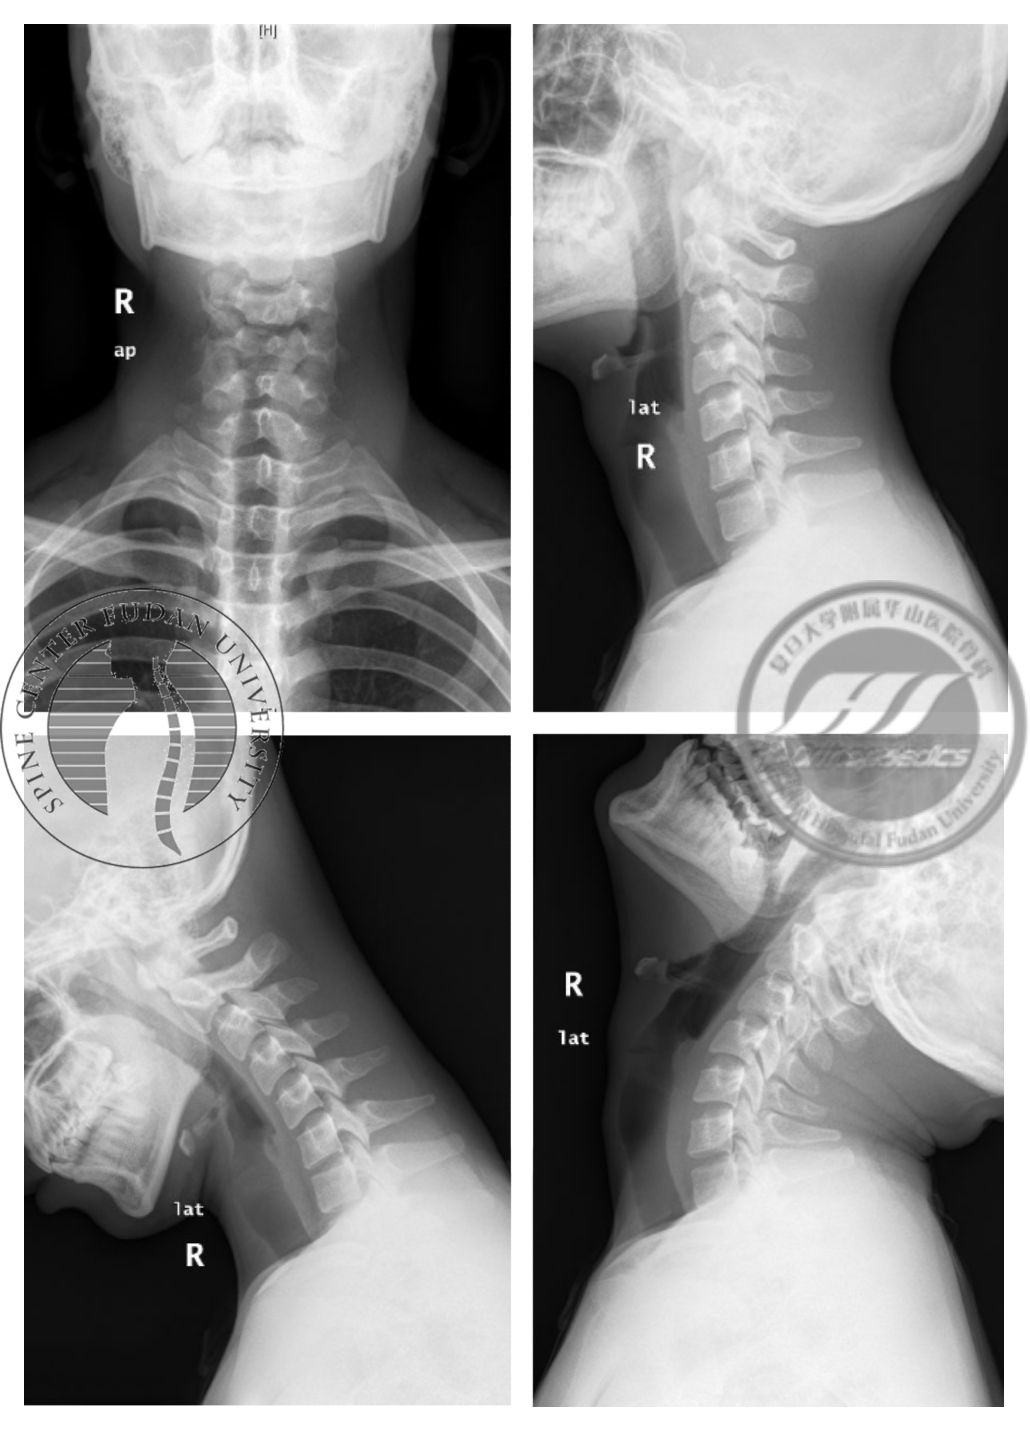

患者,男性,20岁,因“右手肌肉萎缩、无力近4年”于门诊就诊,查体见患者右侧大鱼际、小鱼际肌肉及前臂尺侧肌肉均有萎缩(图2),右手伸指时明显震颤,双下肢无明显肌肉萎缩;无明显感觉异常,右手握力IV级,余肢体肌力V级,双侧膝反射(++),双侧Hoffmann征(-)。患者2017年3月于我院接受神经电生理检查,结果如下(图3),提示下颈段节段性神经源性损害,考虑颈段前角细胞病变可能,部分所检肌存在自发电位及募集减弱。继而接受影像学检查,屈颈位MRI见矢状面T2加权像脊髓后方“膜-壁分离”现象,X线见颈椎曲度变直,活动度正常(图4,5)。门诊拟诊“平山病”,华山分型为Ib型(见表1),嘱佩戴颈托,减少长期低头活动,密切关注病情变化。

图5 颈椎正侧位及过屈过伸位X线,显示患者颈椎生理曲度变直,活动度正常